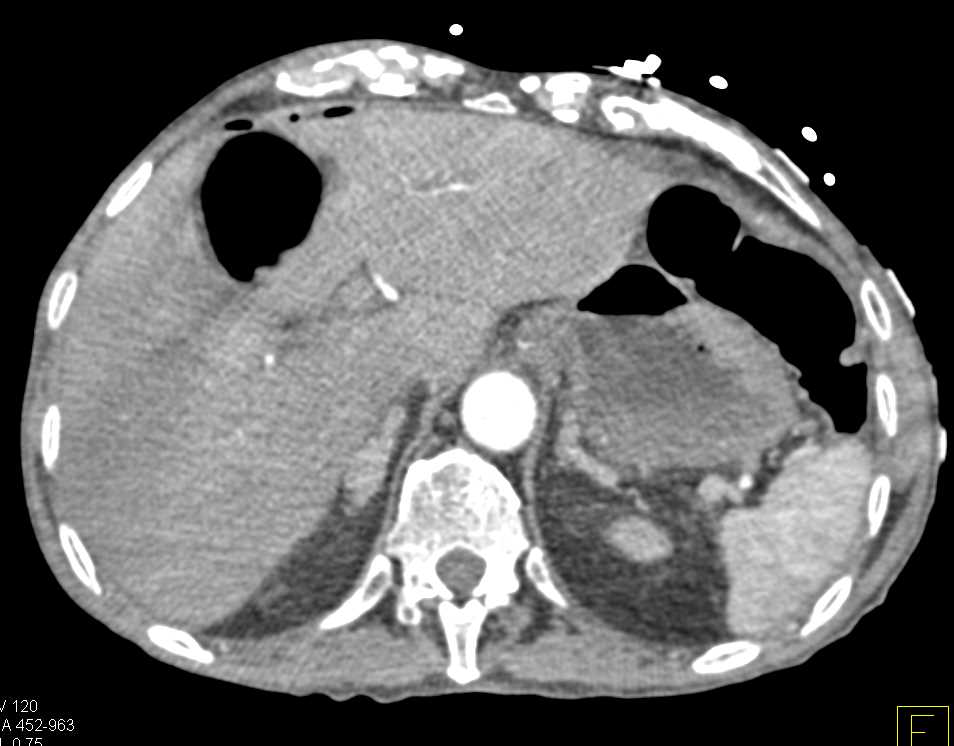

Incidental Bladder Cancer on the Left Wall of the Bladder